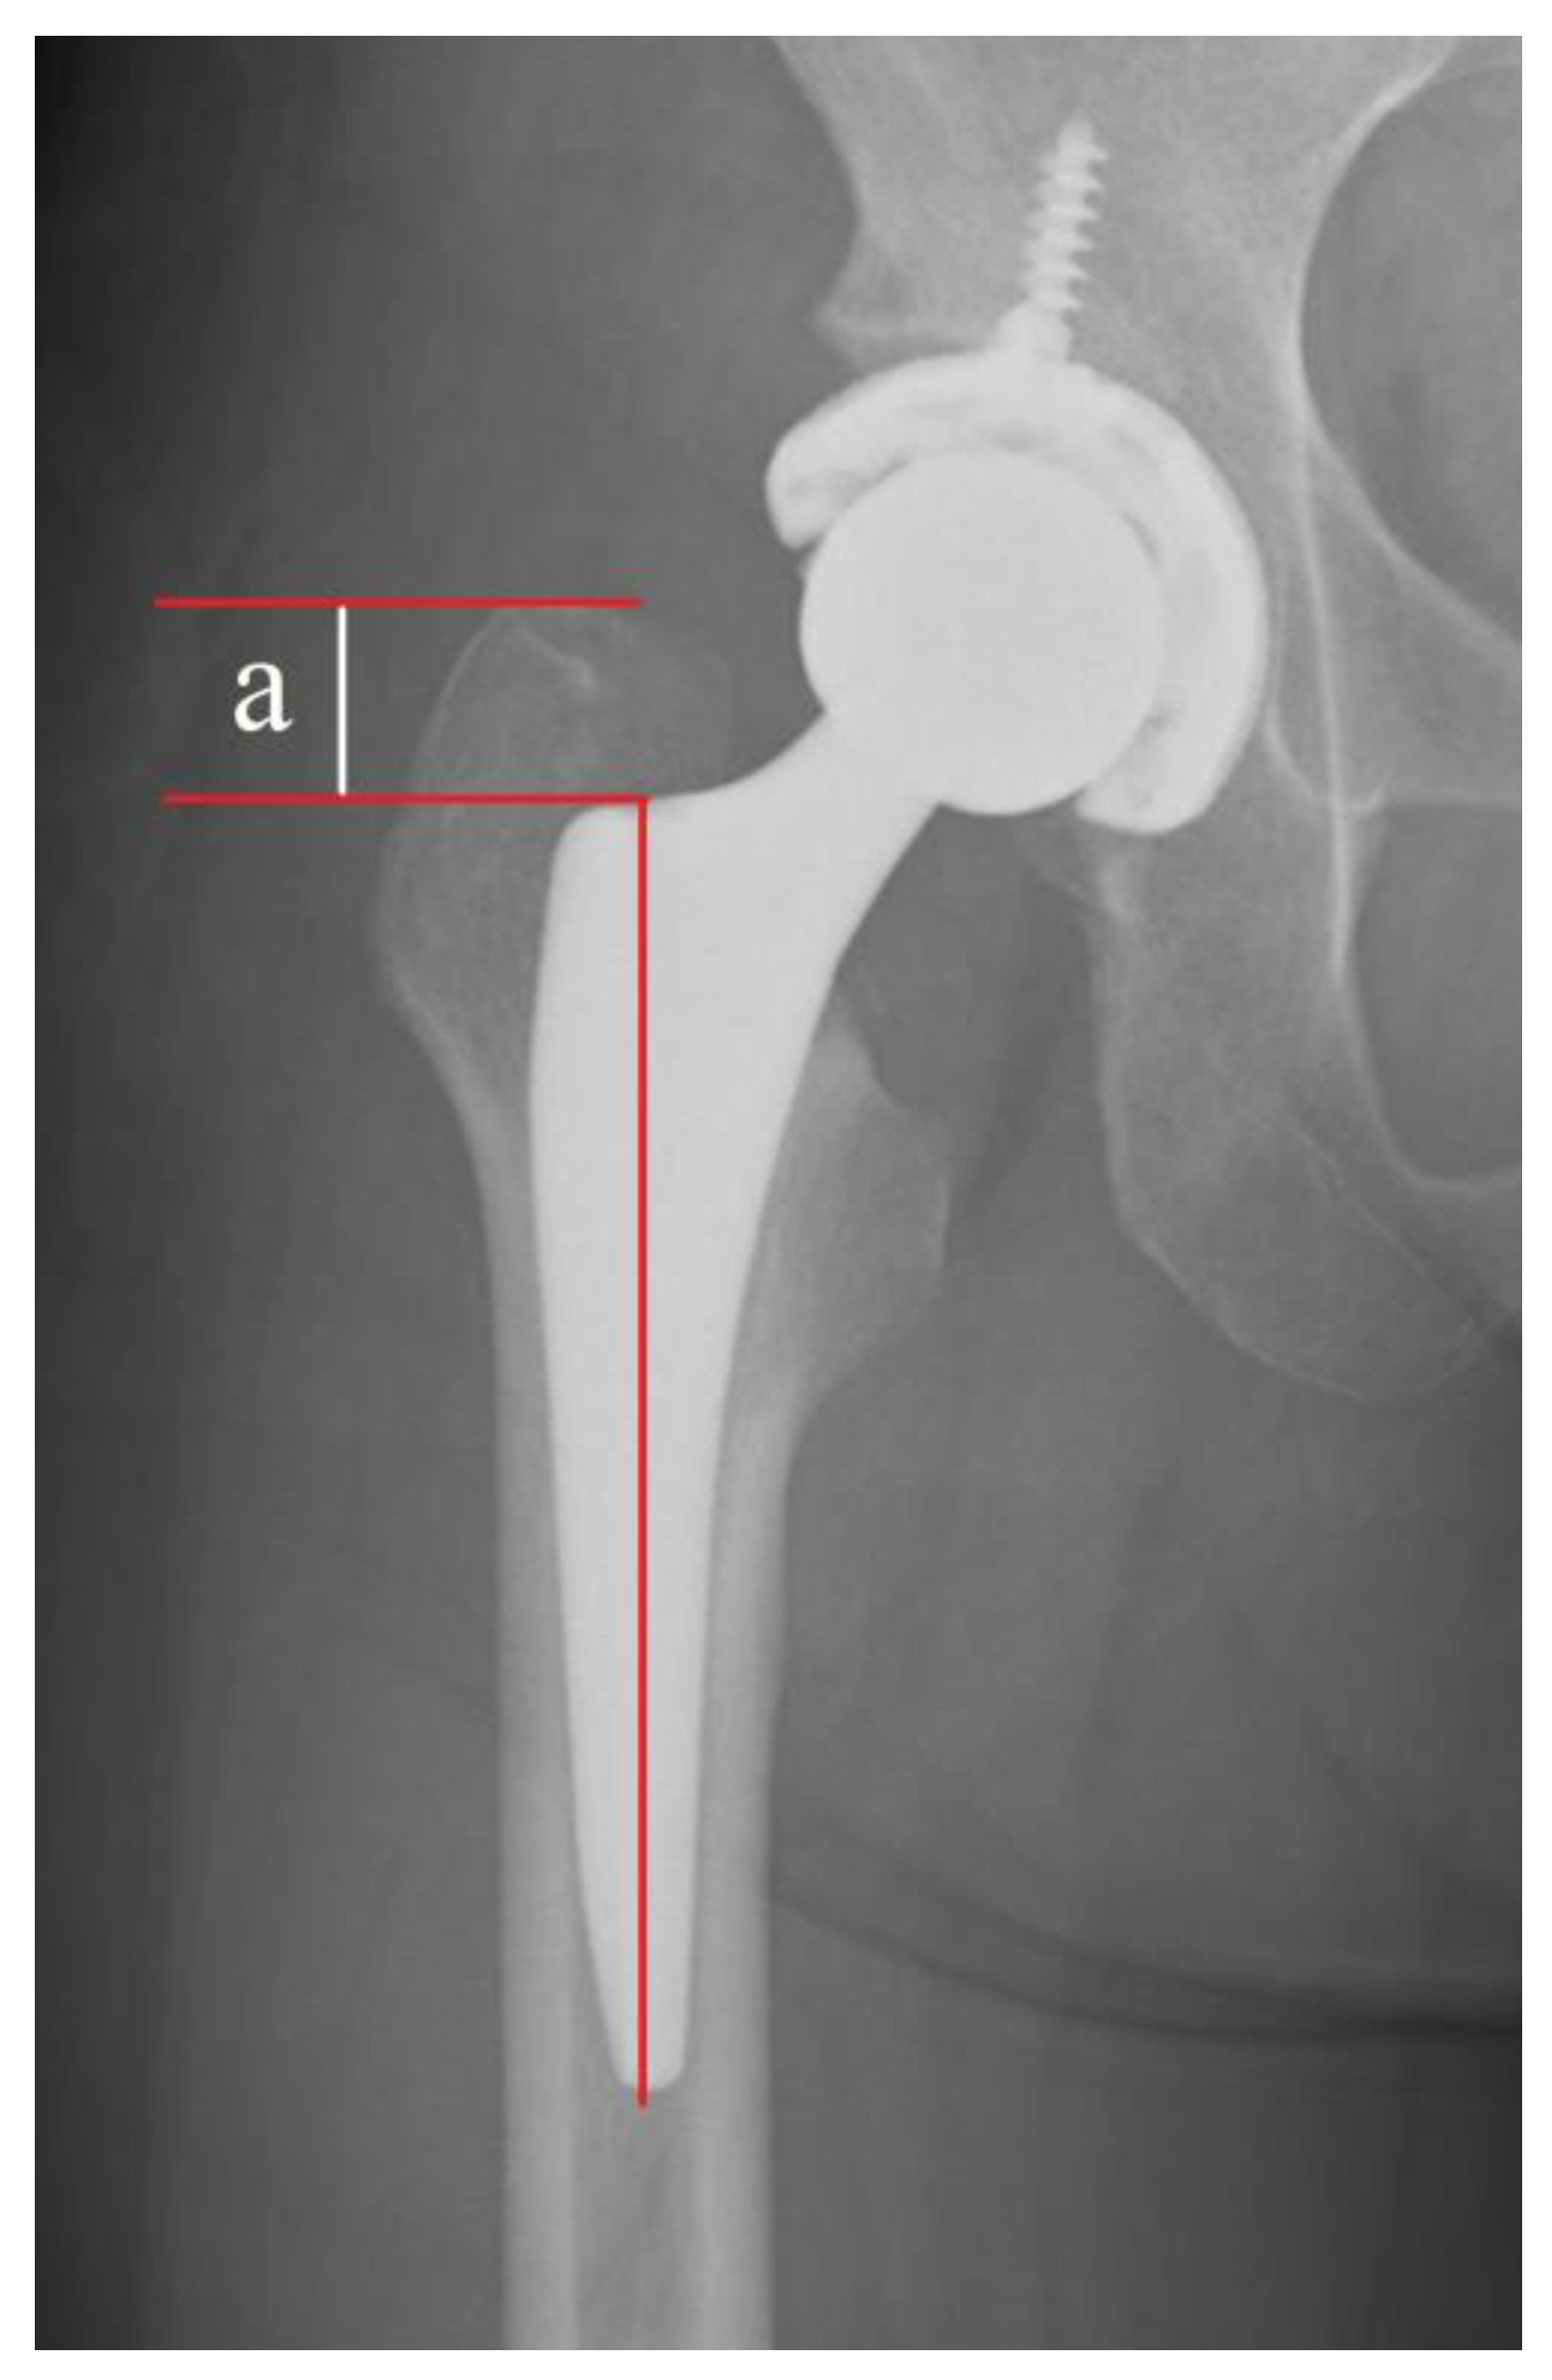

2.4. Radiographic Evaluation